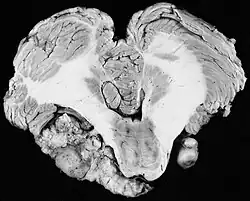

Pierwsze doniesienia o nietypowych przypadkach choroby Recklinghausena pojawiły się w latach 20. i 30. XX wieku. W 1933 Gardner i Frazie opisali pięciopokoleniową rodzinę, w której 38 członków miało utratę słuchu z powodu obustronnych nerwiaków, a 15 z nich dodatkowo straciło wzrok[1]. Inne rodziny opisali Worster-Drought i wsp. w 1937[2], Feiling i Ward w 1920[3], Moyes w 1968[4]. Forster-Drought przypomniał w 1937 roku doniesienie Wisharta z 1822 roku, będące prawdopodobnie pierwszym opisem NF2[5]. Opisany pacjent, Michael Blair, zgłosił się do Wisharta, wówczas prezydenta Królewskiego Towarzystwa Chirurgicznego w Edynburgu, z obustronną głuchotą. Od urodzenia miał niezwykły kształt czaszki i wykrytą około 4. miesiąca życia utratę wzroku w prawym oku. W autopsji stwierdzono guzy opony twardej mózgu i „guz wielkości małego orzecha, bardzo twardy, przyczepiony do obu [nerwów przedsionkowych] w miejscu ich wejścia do przewodu słuchowego wewnętrznego”.

- wyściółczaki (2,5%)[8]. Glejaki włosowatokomoórkowe (gąbczaki) i wyściółczaki zwykle są zlokalizowane w pniu mózgu i górnym odcinku szyjnym rdzenia kręgowego; często współwystępują z jamistością rdzenia lub opuszki. Niekiedy uciskają rdzeń.